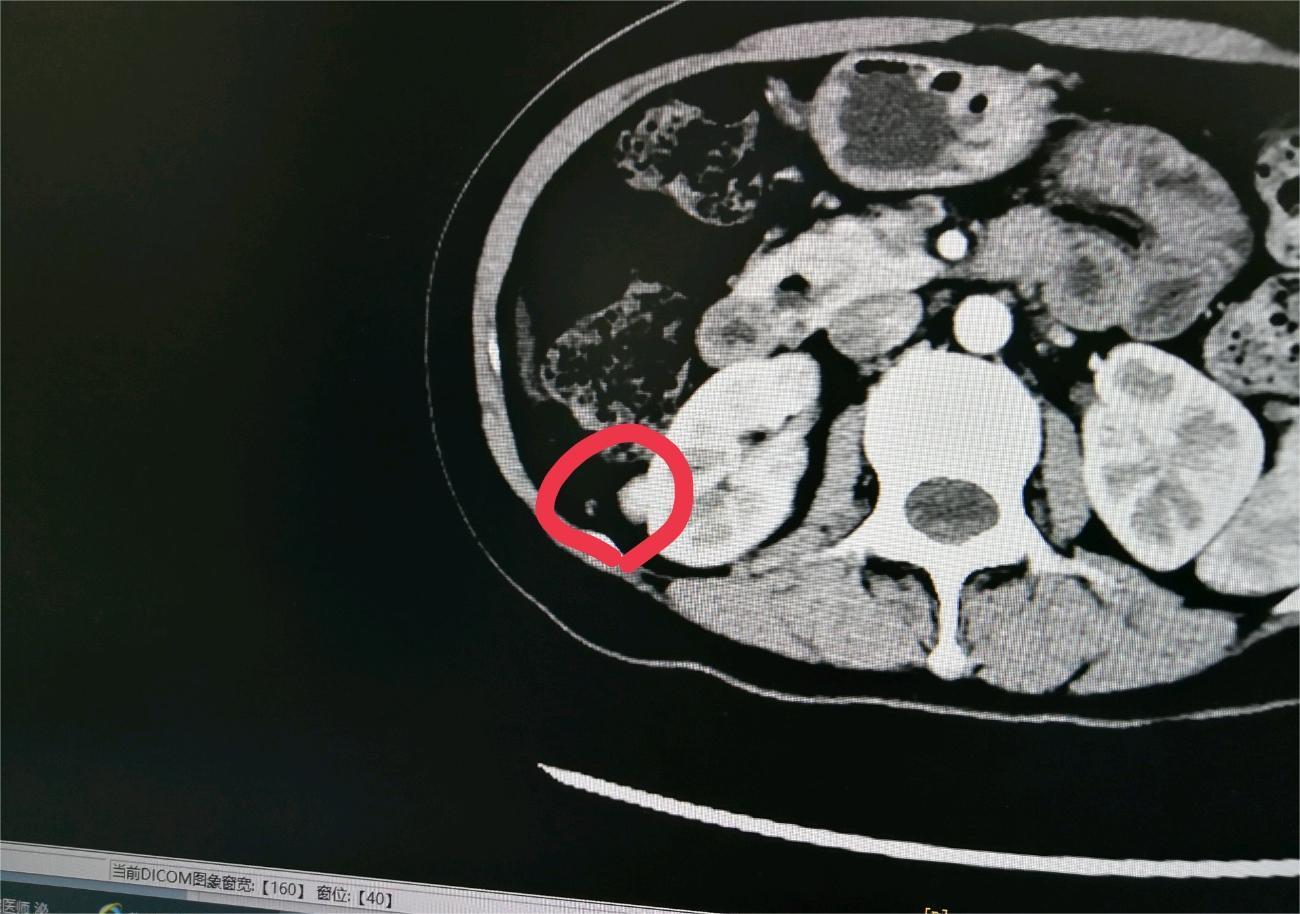

雪落下的季节 02025-02-11 患者家属爸1月份突然出现腰疼不能走路的情况,到医院做检查后发现右肾有个4厘米的肿瘤,怀疑是转移到腰椎!做加强ct后发现腰椎确...